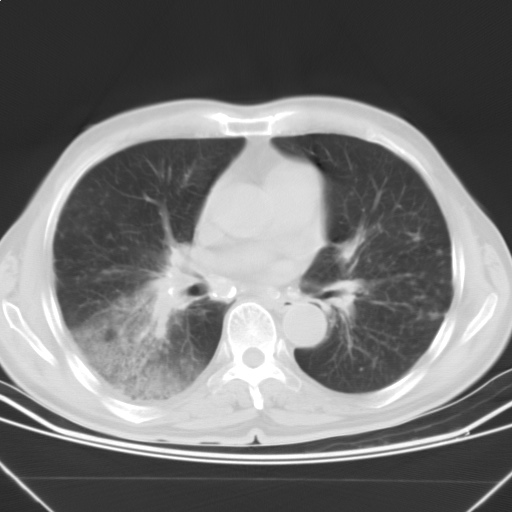

以下是引用随光逐影在2009-5-1 13:53:00的发言:[br]考虑为:1)两肺血行播散型肺结核;2)右肺下叶炎症感染。3)右侧胸膜增厚。